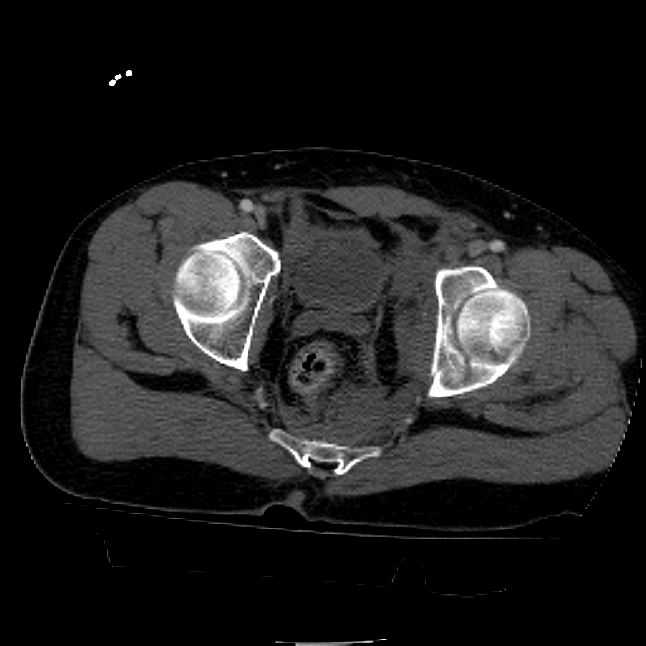

25 yo brittle diabetic, became hypoglycemic and passed out on his motorcycle. Sustained bilateral lateral Hoffa fractures with associated LCL injury on the right and right distal radius fracture. I have questions regarding his pelvic ring/acetabular fracture on the left. Appears to be a very low posterior column fracture with associated posterior wall, marginal impaction. Superior and inferior rami fractures as well on the left giving him a floating segment of inf ramus/ischium/posterior column, but no detectable posterior ring injury. Should the posterior column/posterior wall fracture be addressed surgically because of the marginal impaction? Or is this fracture low enough to be treated non-operatively? I appreciate the input.

I believe the more serious component of the acetabular fracture to be the large (almost 50%) impacted, comminuted zone of the posterior wall. In several series, including the one I reported at the AAOS in 2002 in Dallas of 100 acetabular fractures with posterior wall involvement, all repaired by a single surgeon (Kyle Dickson), those with posterior wall impaction did significantly worse than those without. Nevertheless, the large area of involvement, as well as a joint designed for very low tolerances of "out of round", would indicate that the best chance for avoiding early degenerative changes would be an anatomic repair.

It's an interesting case. The plain films show the impaction, but most of the joint looks pretty good. The CT cuts look awful, though.

The impaction is so big I don't think I would ignore it. It IS down low, but it takes up almost the whole southern hemisphere of his joint.